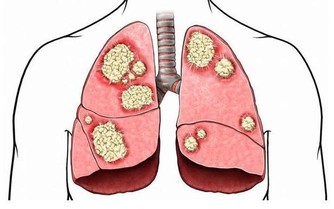

癌症就有一些徵兆,例如不明原因的體重驟減、高燒、極度疲勞、大小便習慣改變、異常出血、黑痣顏色和形狀異常、舌頭顏色異常等。